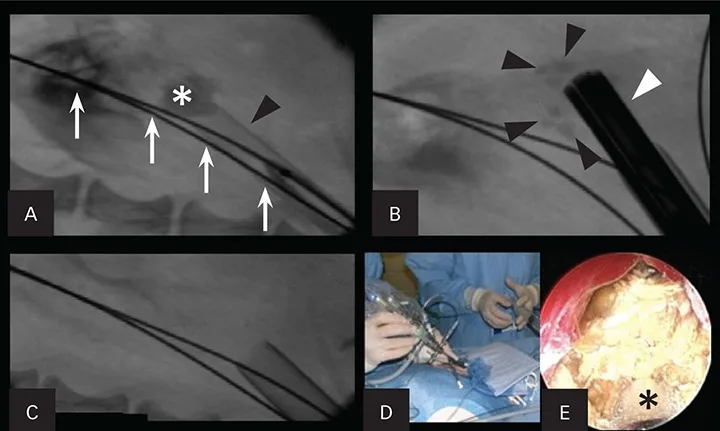

In humans, less invasive methods (eg, extracorporeal shockwave lithotripsy) have been shown to dramatically improve the preservation of renal function. Percutaneous nephrolithotomy (PCNL) can be markedly effective in removing all stone fragments in the calices. In addition, PCNL does not cause injury to the nephrons (Figure 1). Instead, the nephrons are spread apart with the use of a balloon dilation kit to allow a scope and intracorporeal lithotrite to remove the stone debris effectively. This has been shown in humans to be highly renal sparing and has been effective in the author’s practice.

Figure 1. Percutaneous nephrolithotomy in a 3.1-kg female Yorkshire terrier with large nephroliths. Use of a percutaneous access kit under fluoroscopic guidance allows visualization of the large nephrolith (asterisk; A). The access sheath (black arrowhead) is inserted through the renal parenchyma over a dilation balloon. Two safety wires (white arrows) are present. The nephroscope (white arrowhead) is inserted through the sheath onto the stone with a lithotrite, breaking the large stone into fragments (black arrowheads; B). Fluoroscopic image after all stone fragments had been removed from the renal pelvis (C). The nephroscope being placed through the access sheath during percutaneous renal access (D). An endoscopic image of the nephrolith taken during lithotripsy (E). The lithotrite (asterisk) is seen through the working channel of the nephroscope.